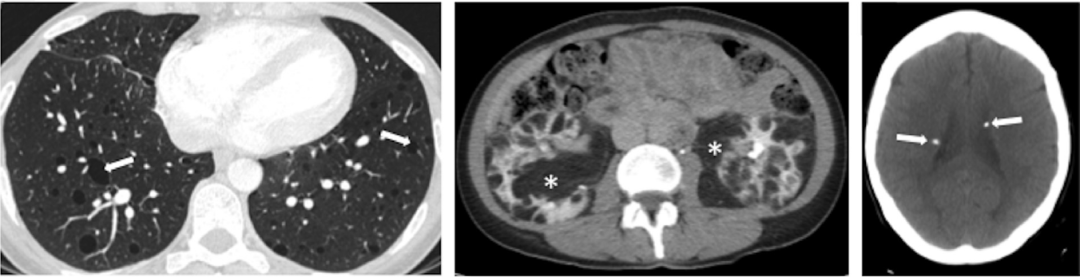

BHD的囊往往会出现比较巨大的泡、有些不规则,靠近下肺和纵膈的情况比较多。

下图也是一个BHD病例,表现为肺部囊性病变+肾脏肿瘤+皮肤异常,提示我们一定鉴别TSC和BHD、要注意肺外表现。

图:BHD,肾透明细胞癌